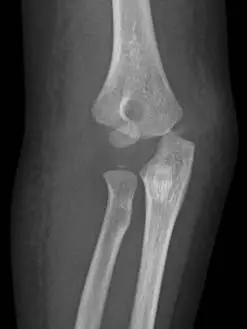

4歲小美由床上跌落,由於右肘的疼痛及腫脹,父母帶她來急診求診,並接受右肘部的 X光檢查,由此 X光影像,顯示此女童發生了何種骨折?

本題提供兩張右肘 X 光影像:

正面(AP)影像: 可見肱骨遠端外側有明顯骨折線,累及外髁(lateral condyle)區域,外側骨折碎片(包含肱骨小頭骨化中心)向外側及下方移位。注意肱骨遠端內側結構(滑車、內上髁)仍保持相對完整,並非完整的髁上骨折表現。骨折線自肱骨幹骺端外側向下延伸至關節面,符合 Milch Type II(骨折線延伸至滑車溝內)的特徵。

綜合影像判讀: 骨折碎片位於外側,累及肱骨小頭骨化中心,位移方向為外側及後側,屬於 Jakob 分類 Type III(移位 > 4